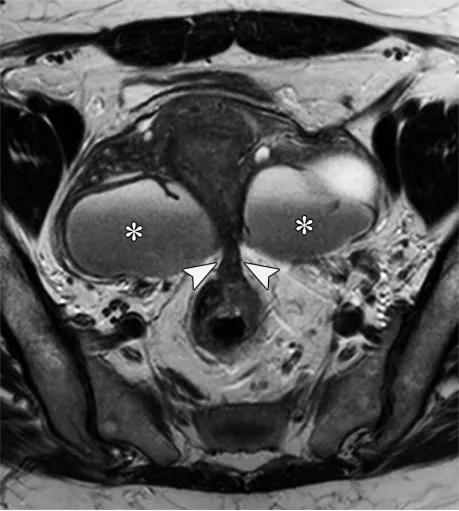

:子宫内膜异位囊肿多为双侧、T1 高信号、T2 “阴影征”(信号降低),伴纤维性 T2 低信号壁;深部子宫内膜异位症表现为 T2 低信号 / DWI 低信号结节,常累及宫骶韧带、直肠乙状结肠等,可导致 “卵巢接吻征”(卵巢被瘢痕牵拉至子宫后方)。

对于卵巢来源的病变,子宫内膜异位囊肿和出血性囊肿是可能的诊断。子宫内膜异位囊肿是子宫内膜异位症的常见表现,子宫内膜异位症影响10%的育龄女性,并与慢性疼痛和不孕相关(10)。子宫内膜异位症的特征是子宫内膜腺体和间质出现在子宫内膜外,导致炎症、纤维化和结构扭曲。影像学检查可能会发现子宫内膜异位囊肿和深部子宫内膜异位症。子宫内膜异位囊肿表现为卵巢囊肿,通常为多灶性和双侧性,由于周期性出血,在T1加权像上呈弥漫性显著高信号,在T2加权像上呈阴影(变暗)改变(图21)。由纤维化和含铁血黄素形成的厚T2低信号 rim、由血块形成的T2低信号斑点以及病变长期存在,均会提高子宫内膜异位囊肿诊断的特异性(65,66)。

图21. 一位20岁痛经女性患者的双侧子宫内膜异位囊肿。(A、B)轴位脂肪抑制T1加权像(A)和T2加权像(B)显示了子宫内膜异位囊肿的典型特征,如双侧T1高信号病灶(A中的*)伴T2信号衰减(B中的*)、T2低信号囊壁以及病灶内T2低信号斑点(B中的箭头),所有这些均提示慢性反复出血。(C)对比增强脂肪抑制T1加权减影图像证实无强化的实性组织。

对于子宫旁/卵巢旁来源的病变,深部子宫内膜异位症是首要考虑的疾病(10)。深部子宫内膜异位症是一种严重的类型,表现为具有腹膜下延伸的纤维化病变。它通常为多灶性,主要累及盆腔,特别是附着于子宫 torus 的宫骶韧带。其他常见的受累部位包括直肠乙状结肠(“蘑菇帽”征)、子宫直肠陷凹、阴道、圆韧带、膀胱和卵巢表面。在晚期病例中,卵巢可能移位至子宫后方,形成“卵巢接吻”征(图27)。深部子宫内膜异位症在T2加权成像和弥散加权成像上表现为低信号增厚区、光滑或毛刺状结节,以及可能牵拉邻近结构并导致结构变形的浸润(例如子宫后屈、子宫偏斜、“卵巢接吻”征和肠管成角)。由于异位子宫内膜腺体中存在血液,深部子宫内膜异位症在T2加权成像和脂肪抑制T1加权成像上偶尔可能出现高信号灶。

图27. 一名46岁女性盆腔疼痛患者的双侧子宫内膜异位囊肿和深部盆腔子宫内膜异位症。轴位T2加权图像显示双侧子宫内膜异位囊肿(*)伴T2信号阴影。在子宫、卵巢和直肠乙状结肠之间可见由深部子宫内膜异位症引起的T2低信号瘢痕(箭头)。这种瘢痕会牵拉结肠,并将卵巢向后移位至子宫,即所谓的卵巢接吻征。